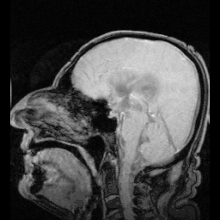

MRI showing flow of CSF

The ventricles are filled with cerebrospinal fluid (CSF) which bathes and cushions the brain and spinal cord within their bony confines. CSF is produced by modified ependymal cells of the choroid plexus found in all components of the ventricular system except for the cerebral aqueduct and the posterior and anterior horns of the lateral ventricles. CSF flows from the lateral ventricles via the interventricular foramina into the third ventricle, and then the fourth ventricle via the cerebral aqueduct in the midbrain. From the fourth ventricle it can pass into the central canal of the spinal cord or into the subarachnoid cisterns via three small foramina: the central median aperture and the two lateral apertures.

According to the traditional understanding of cerebrospinal fluid (CSF) physiology, the majority of CSF is produced by the choroid plexus, circulates through the ventricles, the cisterns, and the subarachnoid space to be absorbed into the blood by the arachnoid villi.

The fluid then flows around the superior sagittal sinus to be reabsorbed via the arachnoid granulations (or arachnoid villi) into the venous sinuses, after which it passes through the jugular vein and major venous system. CSF within the spinal cord can flow all the way down to the lumbar cistern at the end of the cord around the cauda equina where lumbar punctures are performed.